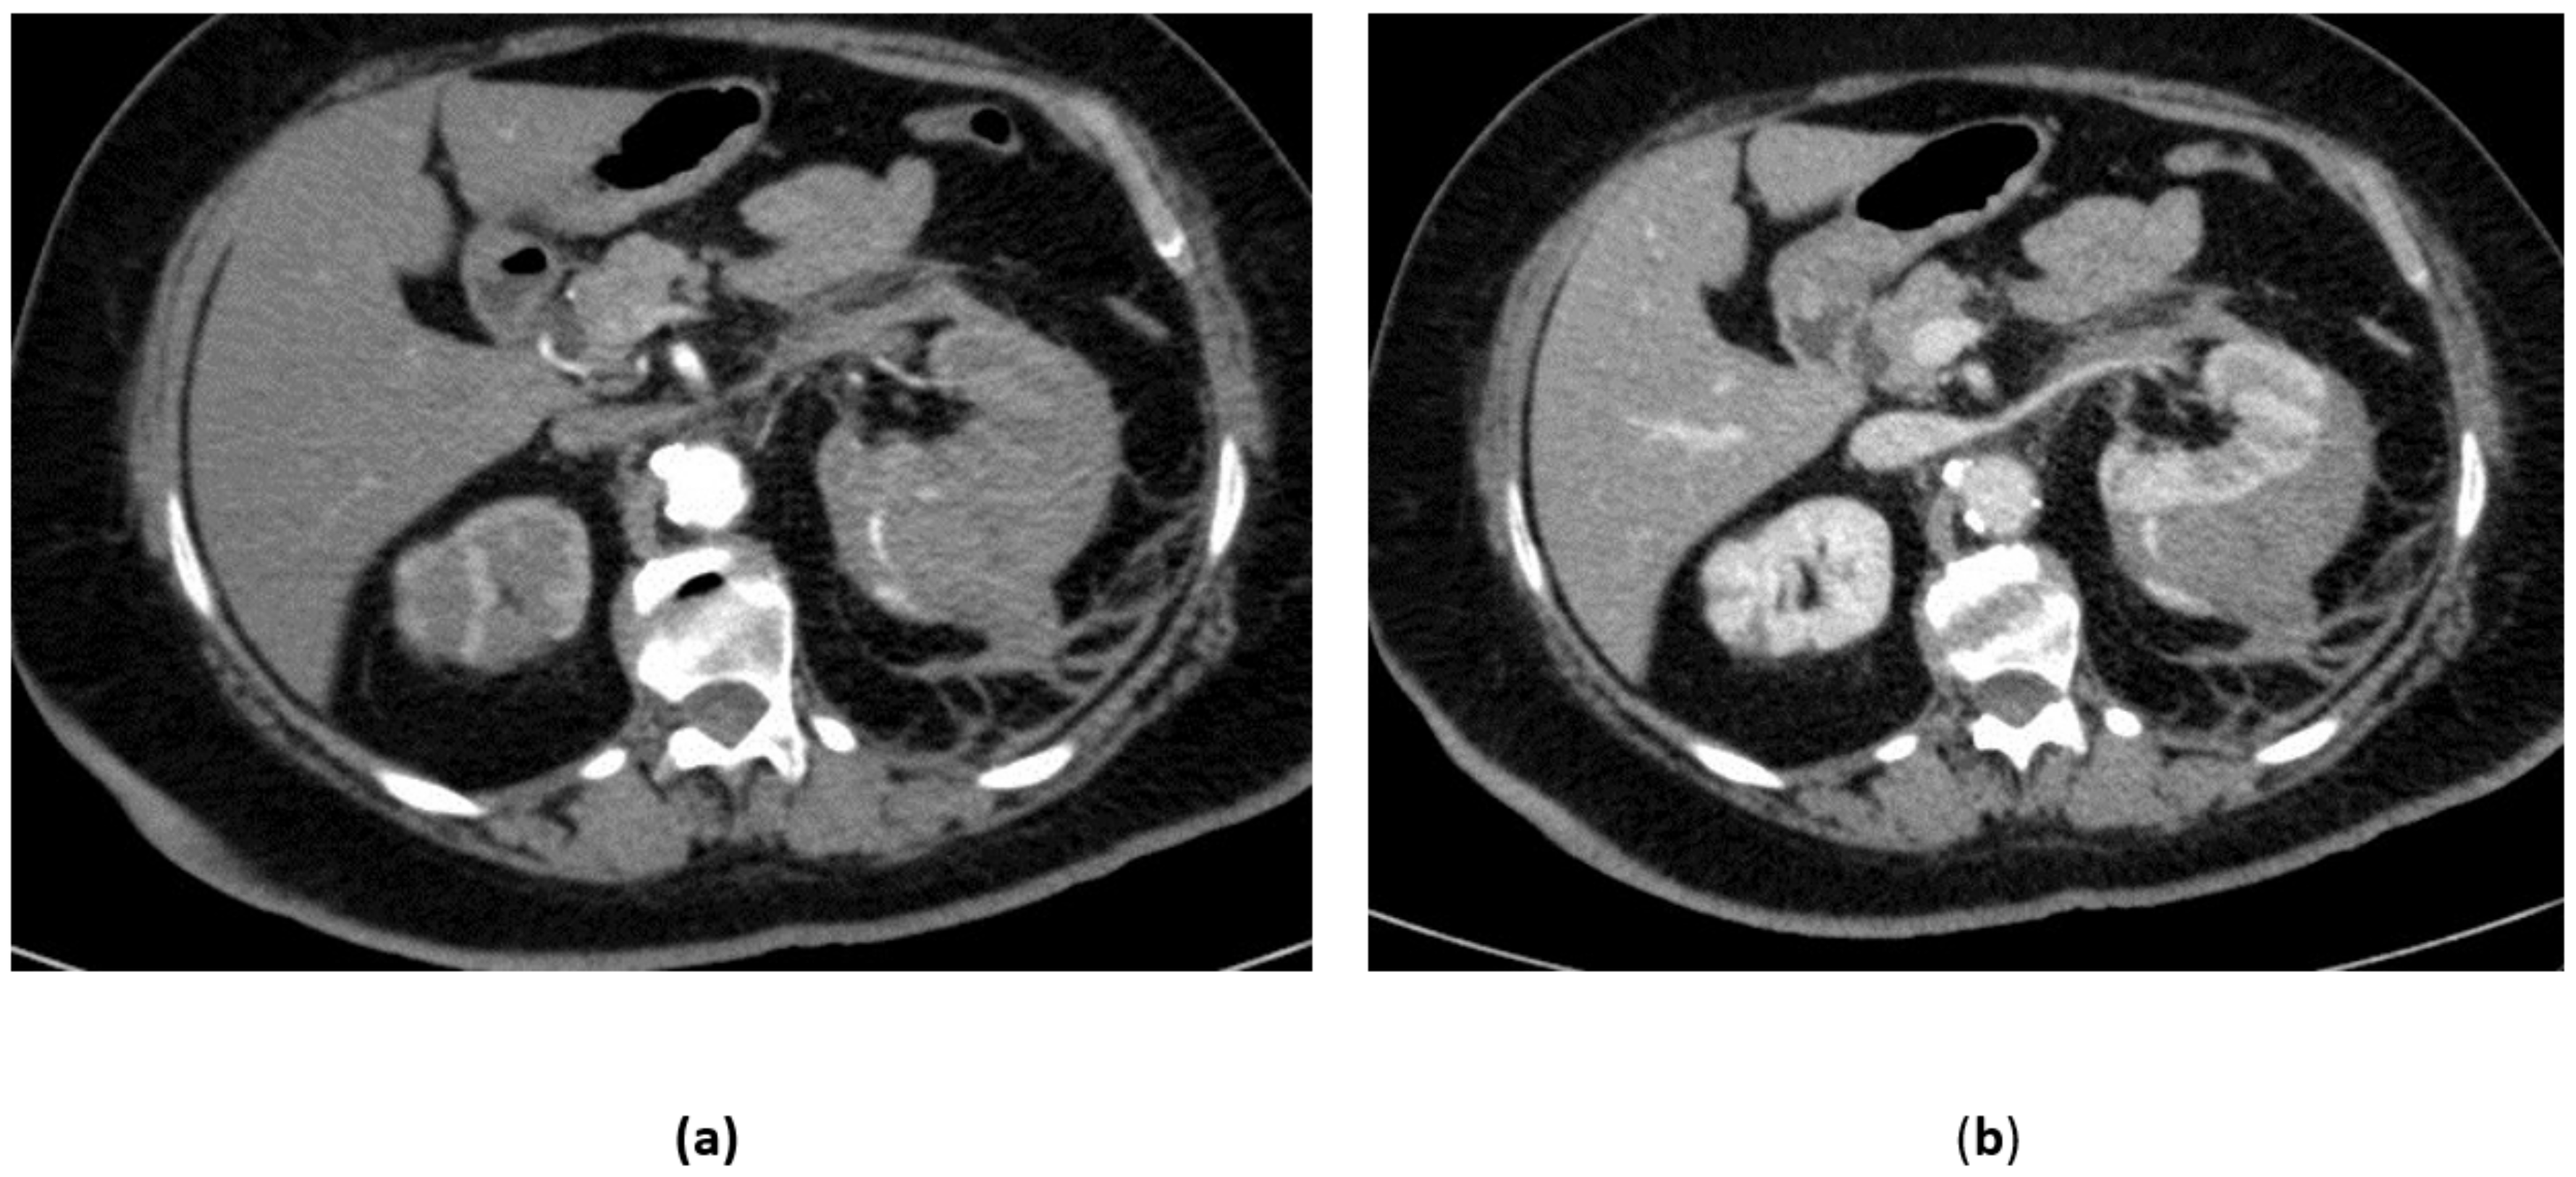

3.4. Renal Trauma

- Grade IV: renal cortical laceration extending into the collecting system, or a segmental renal artery or vein injury (with parenchymal infarct), or main renal artery or vein injury with contained hematoma;

- Grade V: shattered kidney avulsion of the renal pedicle, or thrombosis of the main renal artery.